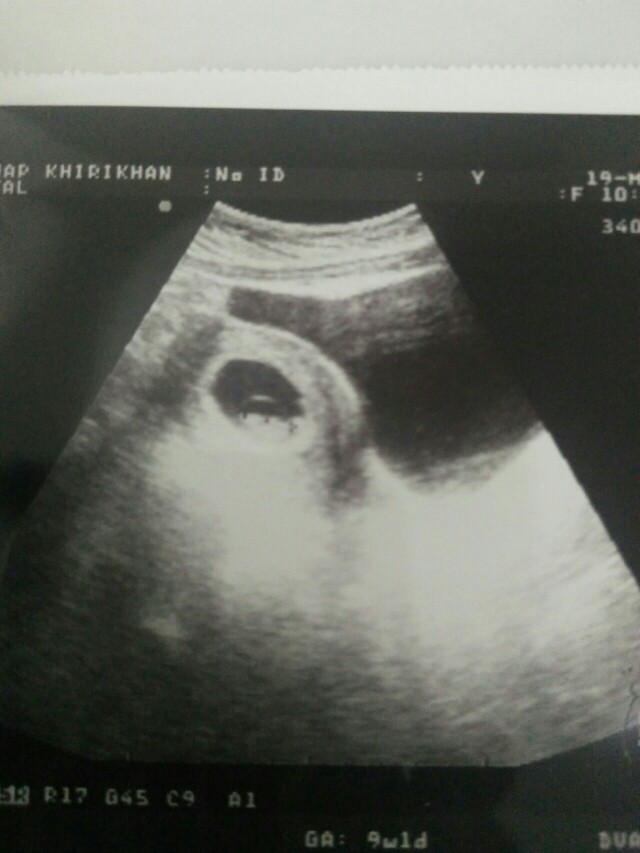

8wซาวด์ครั้งแรกค่ะ